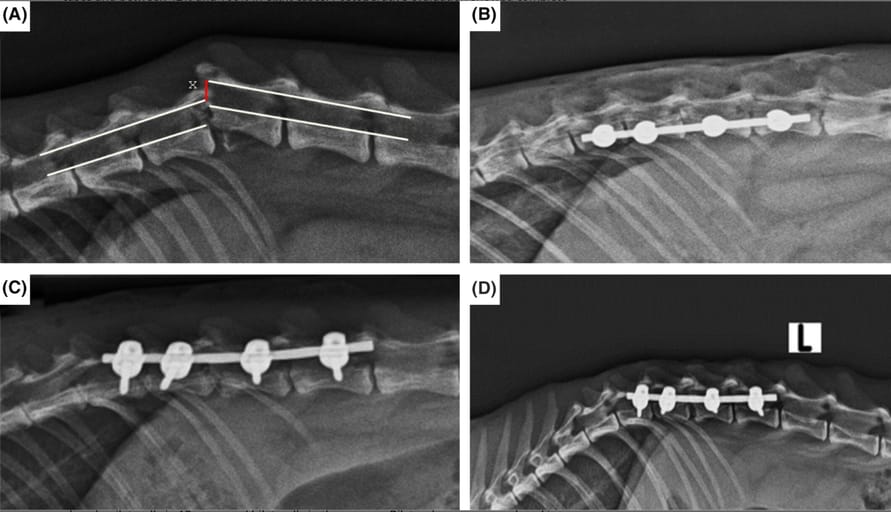

Radiographic evaluation of the degree of vertebral canal displacement (x) and vertebral alignment, preoperatively (A), postoperatively (B), postoperative first week (C), postoperative third week (D).

Lesions were most frequently located between T3–L3 (10 cases) and L4–L7 (6 cases). A total of 50 polyaxial screws were implanted—44 optimally, four with minor breaches (<2 mm), and two were broken but did not require revision. Neurological improvement occurred in 11 cats (69%). Clinical outcomes were rated as excellent in four cats, functional in six, and poor in six. Vertebral alignment was maintained in all cases, and vertebral canal dislocation resolved postoperatively. CT revealed adequate bone stock and screw placement in most cases, with only minor vertebral canal breaches in four screws.